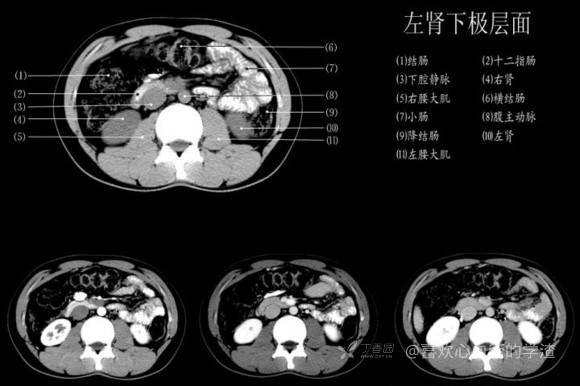

其实你离掌握上腹部 CT 影像只有一套高清实用图谱的距离,下面把我最喜欢的这本图谱分享给大家,为了方便阅读,我加了中文标识。后面附赠几张血管相对位置解剖关系图片,帮助大家理解(文中多图,建议在 wifi 环境下查看)。